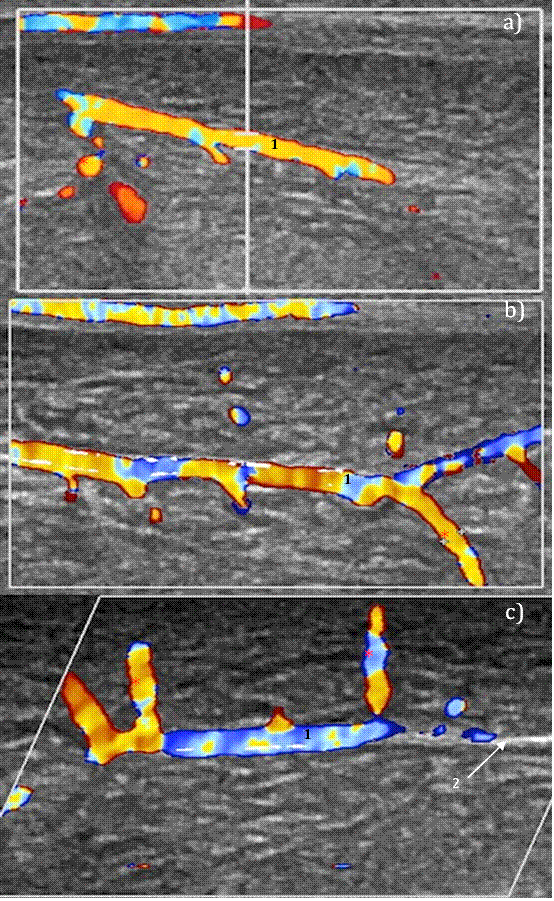

A penile color Doppler ultrasound (CDUS) was performed, using alprostadil 10 mcg (Caverject®). Results showed hyperechoic images following the vascular tract, suggestive of atheromatous plaque in both cavernous arteries, with a diameter of 0.09mm (Figure 1). The registered peak systolic velocity (PSV) was 6.3cm/s before alprostadil injection, and 17.5cm/s 20 minutes after injection (PSV-20). Together with the patient’s medical background, the imaging study findings confirmed severe erectile dysfunction of vascular etiology.

a) Right cavernous artery (RCA)1 pre-injection, with atheromatous plaque2, PSV= 4.61cm/s; b) RCA1 10 min post-injection, atheromatous plaque2 observed, PSV= 17.0cm/s; c) RCA1 20 min post-injection, PSV= 17.5cm/s. Irregular blood flow shown in a), b), and c).

Figure 1 Color Doppler ultrasound of the penis at week 0